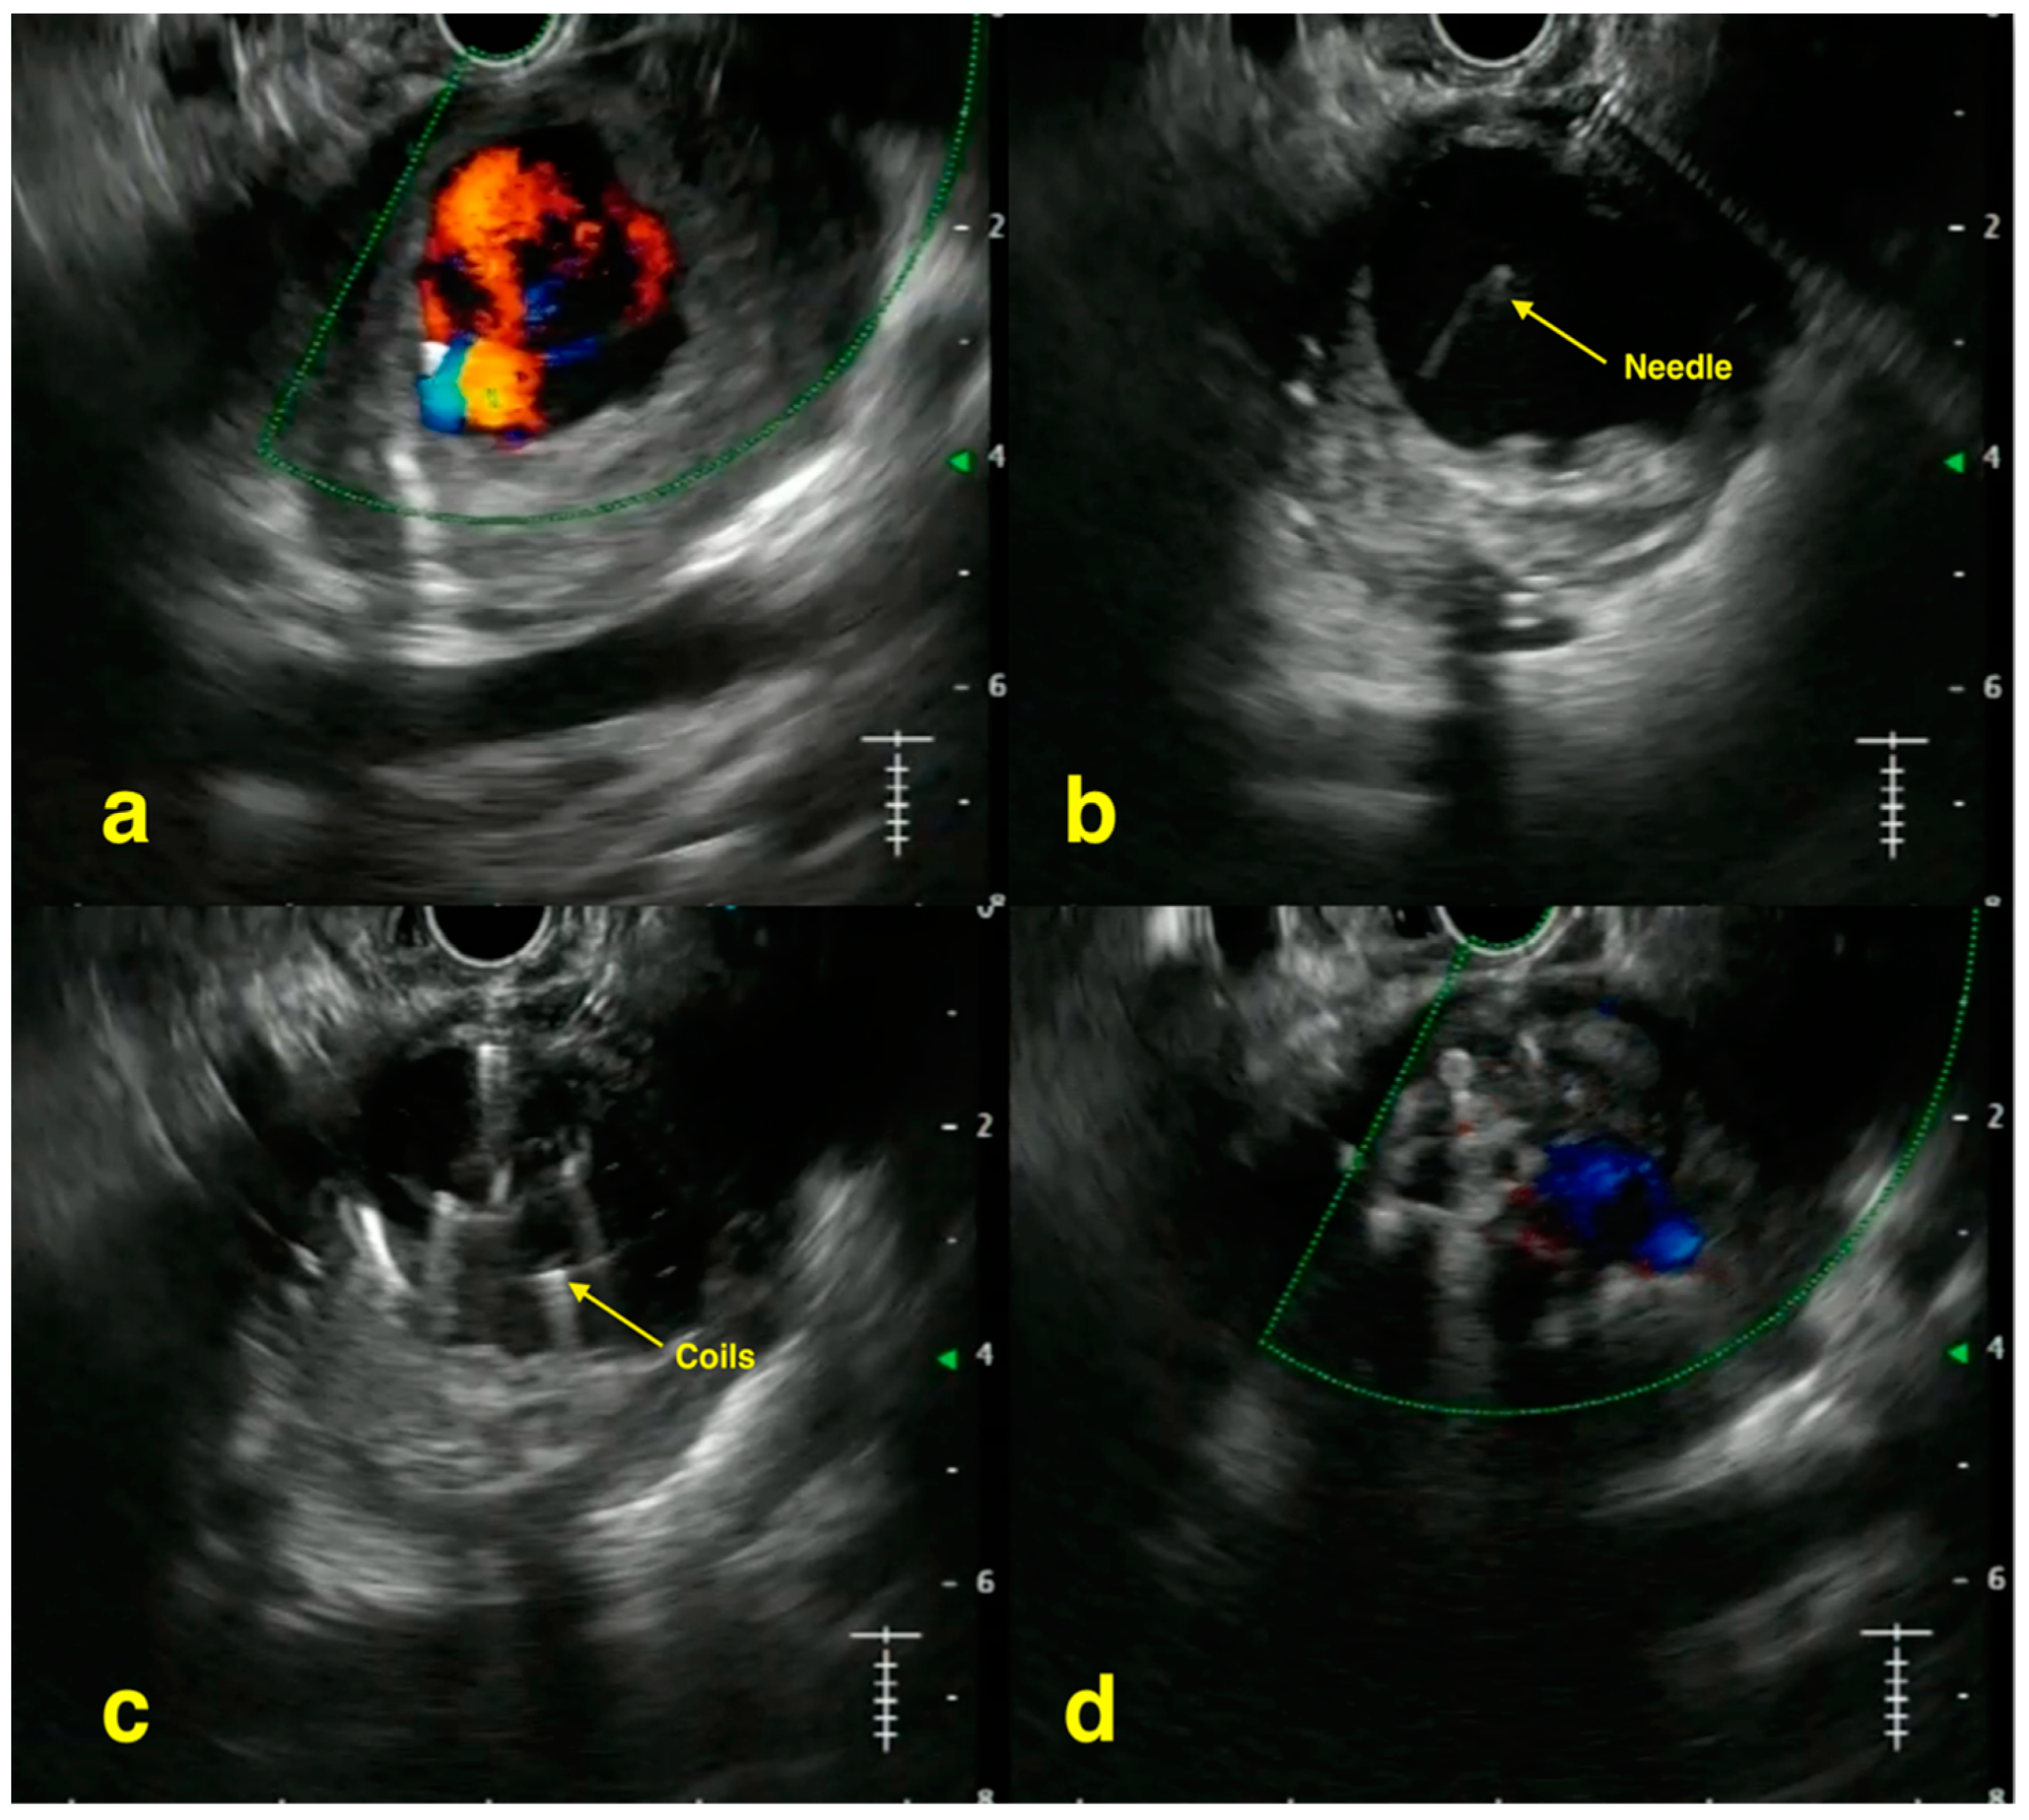

2. EUS-Guided Treatment of Gastric Varices

- Chavan, R.; Baraldo, S.; Patel, N.; Gandhi, C.; Rajput, S. Technical tips for EUS-guided embolization of varices and pseudoaneurysms. VideoGIE 2023, 9, 211–219. [Google Scholar] [CrossRef] [PubMed] [PubMed Central]